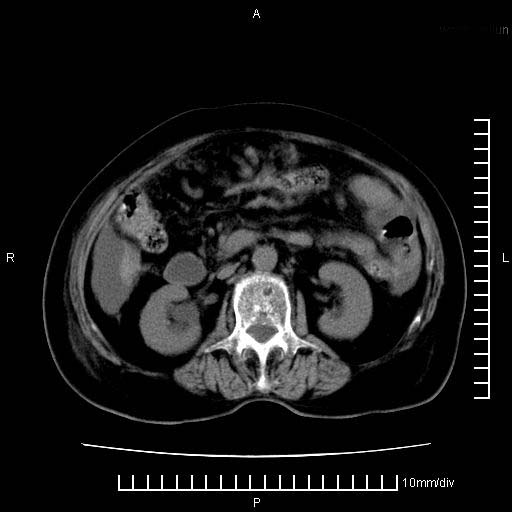

标题: CT28280:腹部增强:女性,80岁

上腹疼痛月余,外院核磁诊断胰腺癌。现临床示右下腹可明显触及包块,可片子上怎么没有看到?

1.胰腺颈体部癌。

2。腹腔积液。

3。右胸腔积液,伴右肺下叶部分萎陷。

4。右肾盂囊肿。

胰腺体部癌累及周围器官,腹膜、粘连

1。胰腺ca伴腹膜腔转移

2。肝左叶低密度灶,考虑转移可能

胰腺体部癌累及周围器官,腹膜、粘连,临床摸到的可能是粘的组织

胰腺结构模糊,胰尾部见囊性包块,周围脂肪密度增高,左肾前筋膜增厚,胸水、腹水。不符合胰腺ca伴腹膜腔转移。考虑胰腺炎伴假性囊肿形成、胸腹腔积液。

右肾盂囊肿。